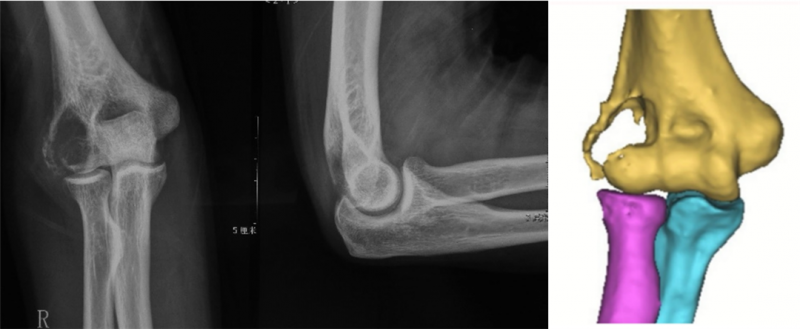

术前影像表现。

据介绍,患者因右肘外侧疼痛就诊于烟台山医院骨病与骨肿瘤科,门诊拍片发现右肱骨远端骨质破坏,经追问病史发现曾因肾癌做过肾切除术,后被诊断为右肱骨远端肾癌骨转移,并收入院。